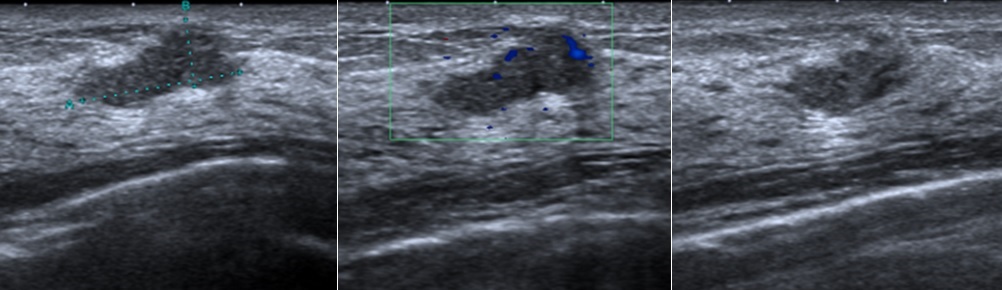

乳房超音波

29歲女性,無生育史、無乳癌家族史。健康檢查經由「乳房超音波」發現:右乳內下側有一個14.8×6.2mm大小的不規則狀腫塊,經切片證實為乳癌,因早期發現而即時手術,恢復良好。